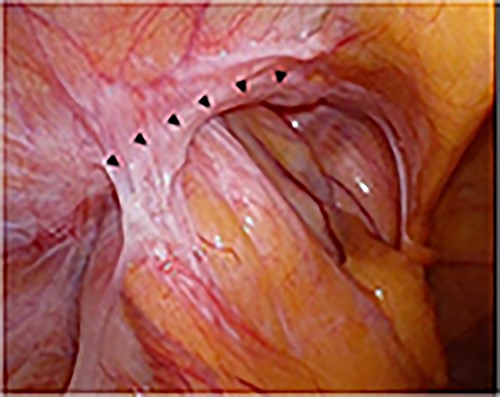

A laparoscope was inserted through a 12-mm umbilical port. Another 12-mm port was created at the level of the umbilicus aligning with the right mid-clavicle, and a 5-mm port was placed on the contralateral side of the line connecting the hernial orifice to the umbilicus. The bulging in the abdominal cavity caused by the hernia’s content could be observed in the laparoscopic view (Fig. 3A). Laparoscopic reduction was successfully performed, and a small segment of the incarcerated bowel was mildly erythematous. Therefore, we decided that bowel resection was unnecessary. After observing the hernial orifice, we found that the peritoneum with the right medial umbilical fold was easily turned inward into the abdominal cavity, suggesting a type of sliding hernia involving the medial umbilical folds [7], and the hernial orifice could not be identified (Fig. 3B). After the peritoneal incision and dissection, the hernial orifice was found lateral to the right epigastric artery. However, although the inner inguinal ring was small, the hernial orifice was observed under the transversus aponeurotic arch in the ventral–lateral direction (Fig. 4A). By pressing the inguinal region from the body surface, the hernial orifice could be recognized more easily (Fig. 4B). The size of the hernial orifice was ~20 mm. Based on the aforementioned findings, the patient was rediagnosed with right interparietal inguinal hernia. After diagnosis, laparoscopic preperitoneal hernia repair was performed with a mesh using the same surgical procedure as that for a standard transabdominal preperitoneal (TAPP) repair. In addition, the edge of mesh was placed ≥3 cm from the hernial orifice, and the center of the mesh was slightly ventral and lateral to the internal inguinal ring.

Intraoperative findings of right inguinal region after peritoneal incision; the black triangles show the hernial orifice; the dotted circle indicates the assumed hernia sac; the black cross indicates the internal inguinal ring (A); by pressing the inguinal region from the body surface, intermuscular soft tissue was prolapsed into the abdominal cavity (B).